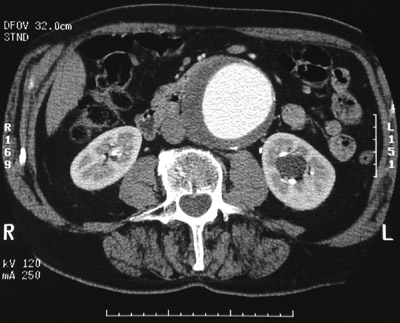

![]() | This abdominal CT scan with contrast reveals an abdominal aortic aneurysm that extended from just below the renal arteries past the takeoff of the inferior mesenteric artery. Note the bright contrast material filling the lumen with surrounding mural thrombus that is darker. The total diameter is approximately 7 to 8 cm in diameter, in great danger of rupture. A pulsatile abdominal mass was palpable. |